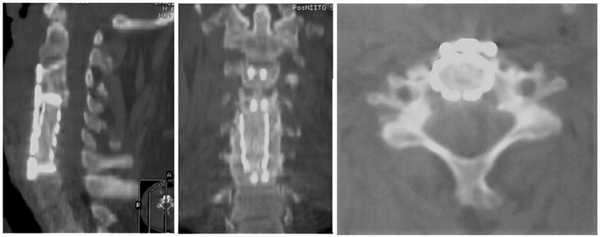

Выполнена операция: дискэктомия СIII—СIV, СIV—СV, СV—СVI, СVI—СVII, корпорэктомия СV, СVI, удаление оссифицированной задней продольной связки, оссифицированных грыж дисков, декомпрессия спинного мозга и корешков на уровне СIV—СVI, коррекция деформации позвоночника, корпородез СIII—СIV кейджем, СIV—СVI — меш-кейджем с фиксацией пластиной (рис. 3). Рис. 3. МСКТ-контроль (сагиттальная, коронарная, аксиальная проекции).

Учитывая отсутствие признаков компрессии спинного мозга на уровне С3—С4, нестабильности на этом уровне при декомпенсации деформации и ее нарастании, резекция тела позвонка не проводилась. На этом уровне выполнена дискэктомия, что позволило после редукции усилить стабильность оперированного сегмента двумя винтами.